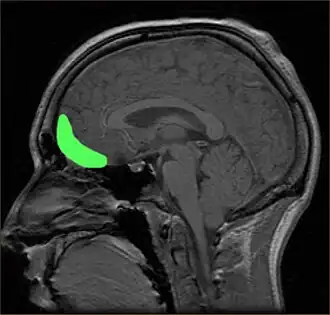

![]() Approximate location of the OFC shown on a sagittal MRI | |

The orbitofrontal cortex (OFC) is a prefrontal cortex region in the frontal lobes of the brain which is involved in the cognitive process of decision-making. In non-human primates it consists of the association cortex areas Brodmann area 11, 12 and 13; in humans it consists of Brodmann area 10, 11 and 47.[1]

The OFC is functionally related to the ventromedial prefrontal cortex.[2] Therefore, the region is distinguished due to the distinct neural connections and the distinct functions it performs.[3] It is defined as the part of the prefrontal cortex that receives projections from the medial dorsal nucleus of the thalamus, and is thought to represent emotion, taste, smell and reward in decision-making.[4][5][6][7][8][9][10][11] It gets its name from its position immediately above the orbits in which the eyes are located. Considerable individual variability has been found in the OFC of humans.[12] A related area is found in rodents.[13]